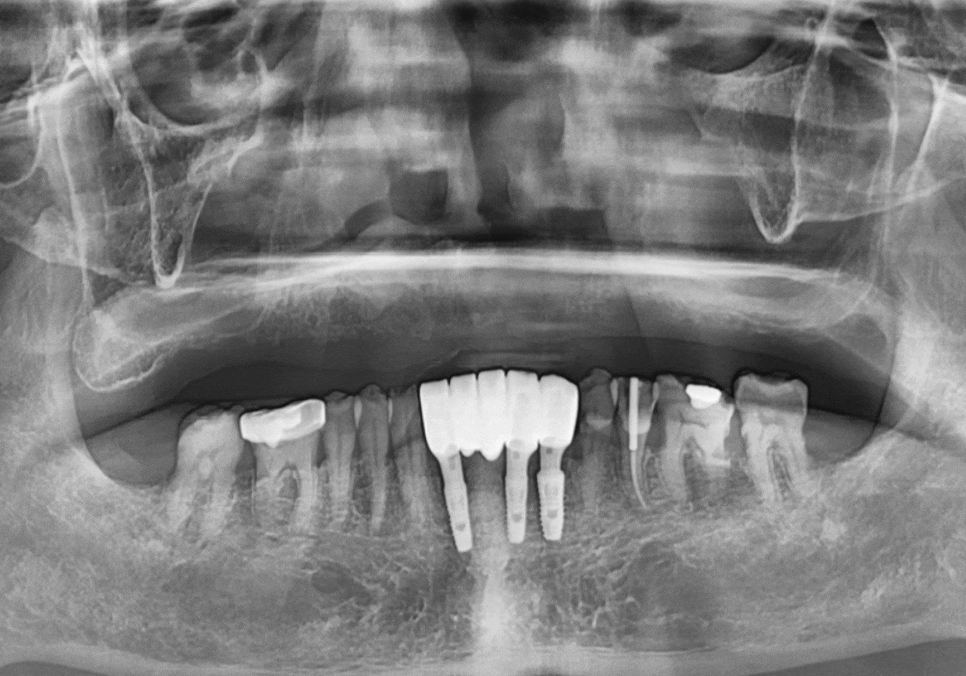

방사선 사진을 보니

잇몸뼈가 전체적으로 아주 얇아져 있었죠.

전체적으로 뼈가 얇았기에,

CT 정밀 분석을 통해

그나마 뼈 상태가 양호한 부위를

전략적으로 선택했습니다.

총 6개의 임플란트를 심고

보철로 연결해 12개의 치아를

만드는 계획을 세웠죠.